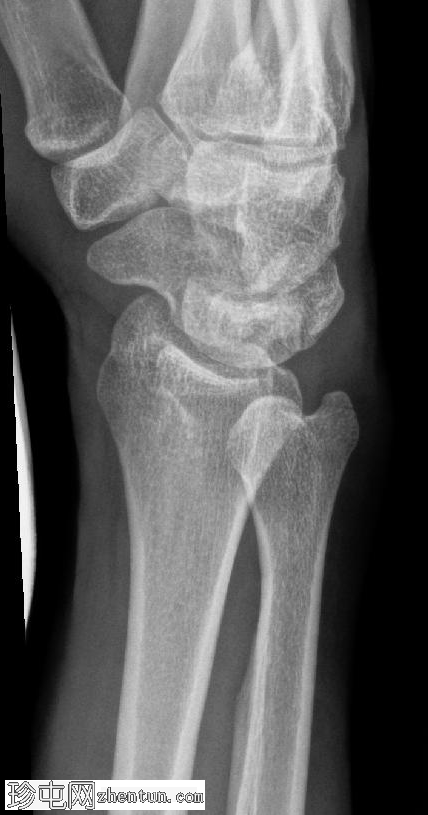

斜位片

可见豌豆骨皮质明显中断,并伴有一小块邻近骨碎片,符合皮质骨折的表现。此外,其上方软组织肿胀,提示急性骨折。

尺骨茎突可见透亮区,符合无移位尺骨茎突骨折的表现。